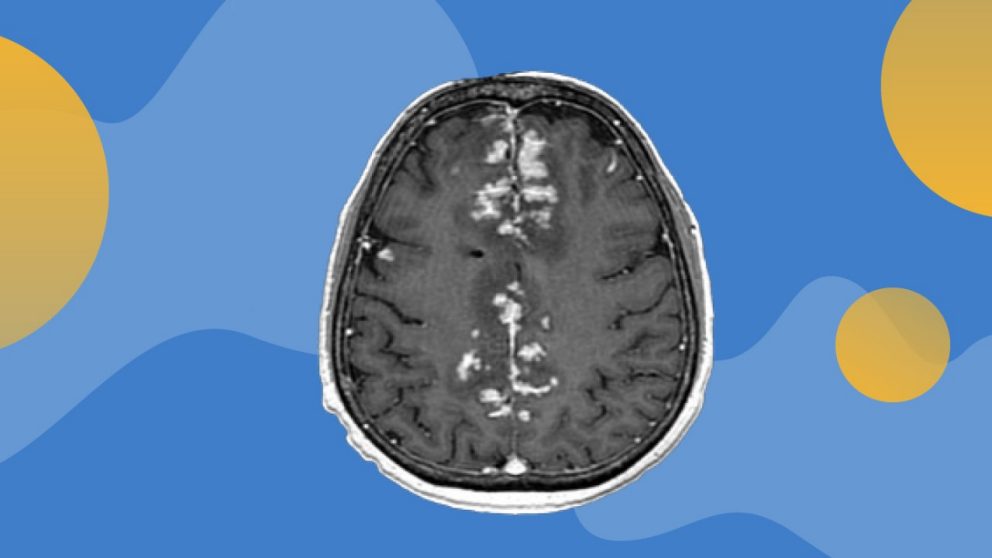

Leptomeningeal disease is a complication of cancer that occurs when cancer cells from primary tumors migrate into the cerebrospinal fluid (CSF) and leptomeninges, the outer lining of the brain and spinal cord. These cells can quickly spread throughout the CSF and cause a wide variety of neurological symptoms. Roughly 10% of patients with stage IV melanoma will be diagnosed with LMD, which also commonly derives from metastatic lung cancer and breast cancer.

Intrathecal administration has been studied in other settings. A previous proof-of-concept study by Glitza Oliva and colleagues at MD Anderson demonstrated that IT administration of interleukin-2 in patients with LMD had encouraging results but was associated with serious side effects. This new study showed that injecting nivolumab directly into the spinal fluid increases its concentration within the CSF, since these antibodies cannot otherwise easily penetrate the blood-brain barrier